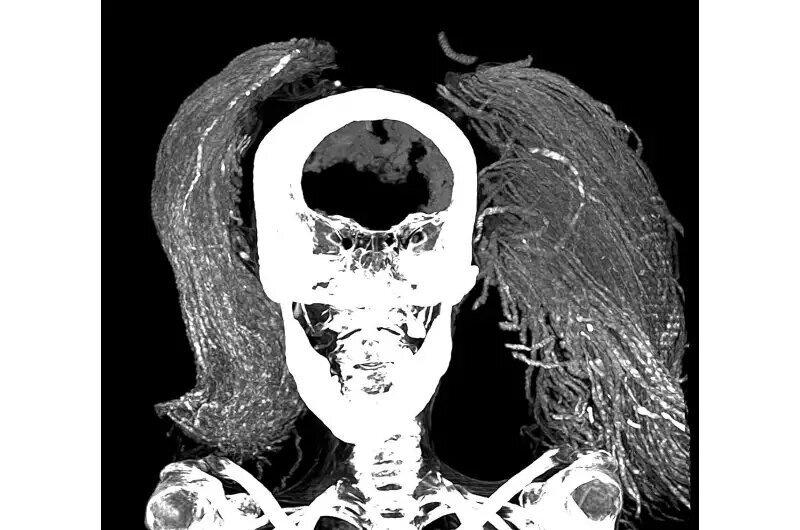

در پژوهش اخیر، سلیم از سیتیاسکن برای تشریح مجازی مومیایی و تخمین سن او، شناسایی آسیبشناسیها و وضعیت نگهداری او استفاده کرد. او و همکارش دکتر سامیه المرقانی از فنهای پیشرفتهای مانند میکروسکوپ الکترونی روبشی (SEM)، طیفسنجی تبدیل فوریه فروسرخ (FTIR) و آنالیز پراش اشعه ایکس (XRD) برای شناسایی مواد استفاده کردند.

سلیم از تصاویر CT دوبعدی و سهبعدی تخمین زد که قد زن در زمان زندگی ۱.۵۴ متر بوده است. بر اساس مورفولوژی مفصل بین دو استخوان لگن، که با افزایش سن صاف میشود، تصاویر سی تی تخمین زدند که او در زمان مرگ تقریباً ۴۸ سال سن داشته است. او از آرتریت خفیف ستون فقرات رنج میبرد که از وجود استئوفیتها یا خارهای استخوانی روی مهرهها مشهود بود.

همچنین هیچ برشی بر بدن مومیایی پیدا نشد و این بااینکه مغز، دیافراگم، قلب، ریهها، کبد، طحال، کلیهها و روده هنوز وجود دارند، مطابقت داشت. این تعجبآور بود، زیرا روش کلاسیک مومیایی در پادشاهی جدید (۱۵۵۰-۱۰۶۹ قبل از میلاد) شامل برداشتن همه این اندامها بهجز قلب بود.